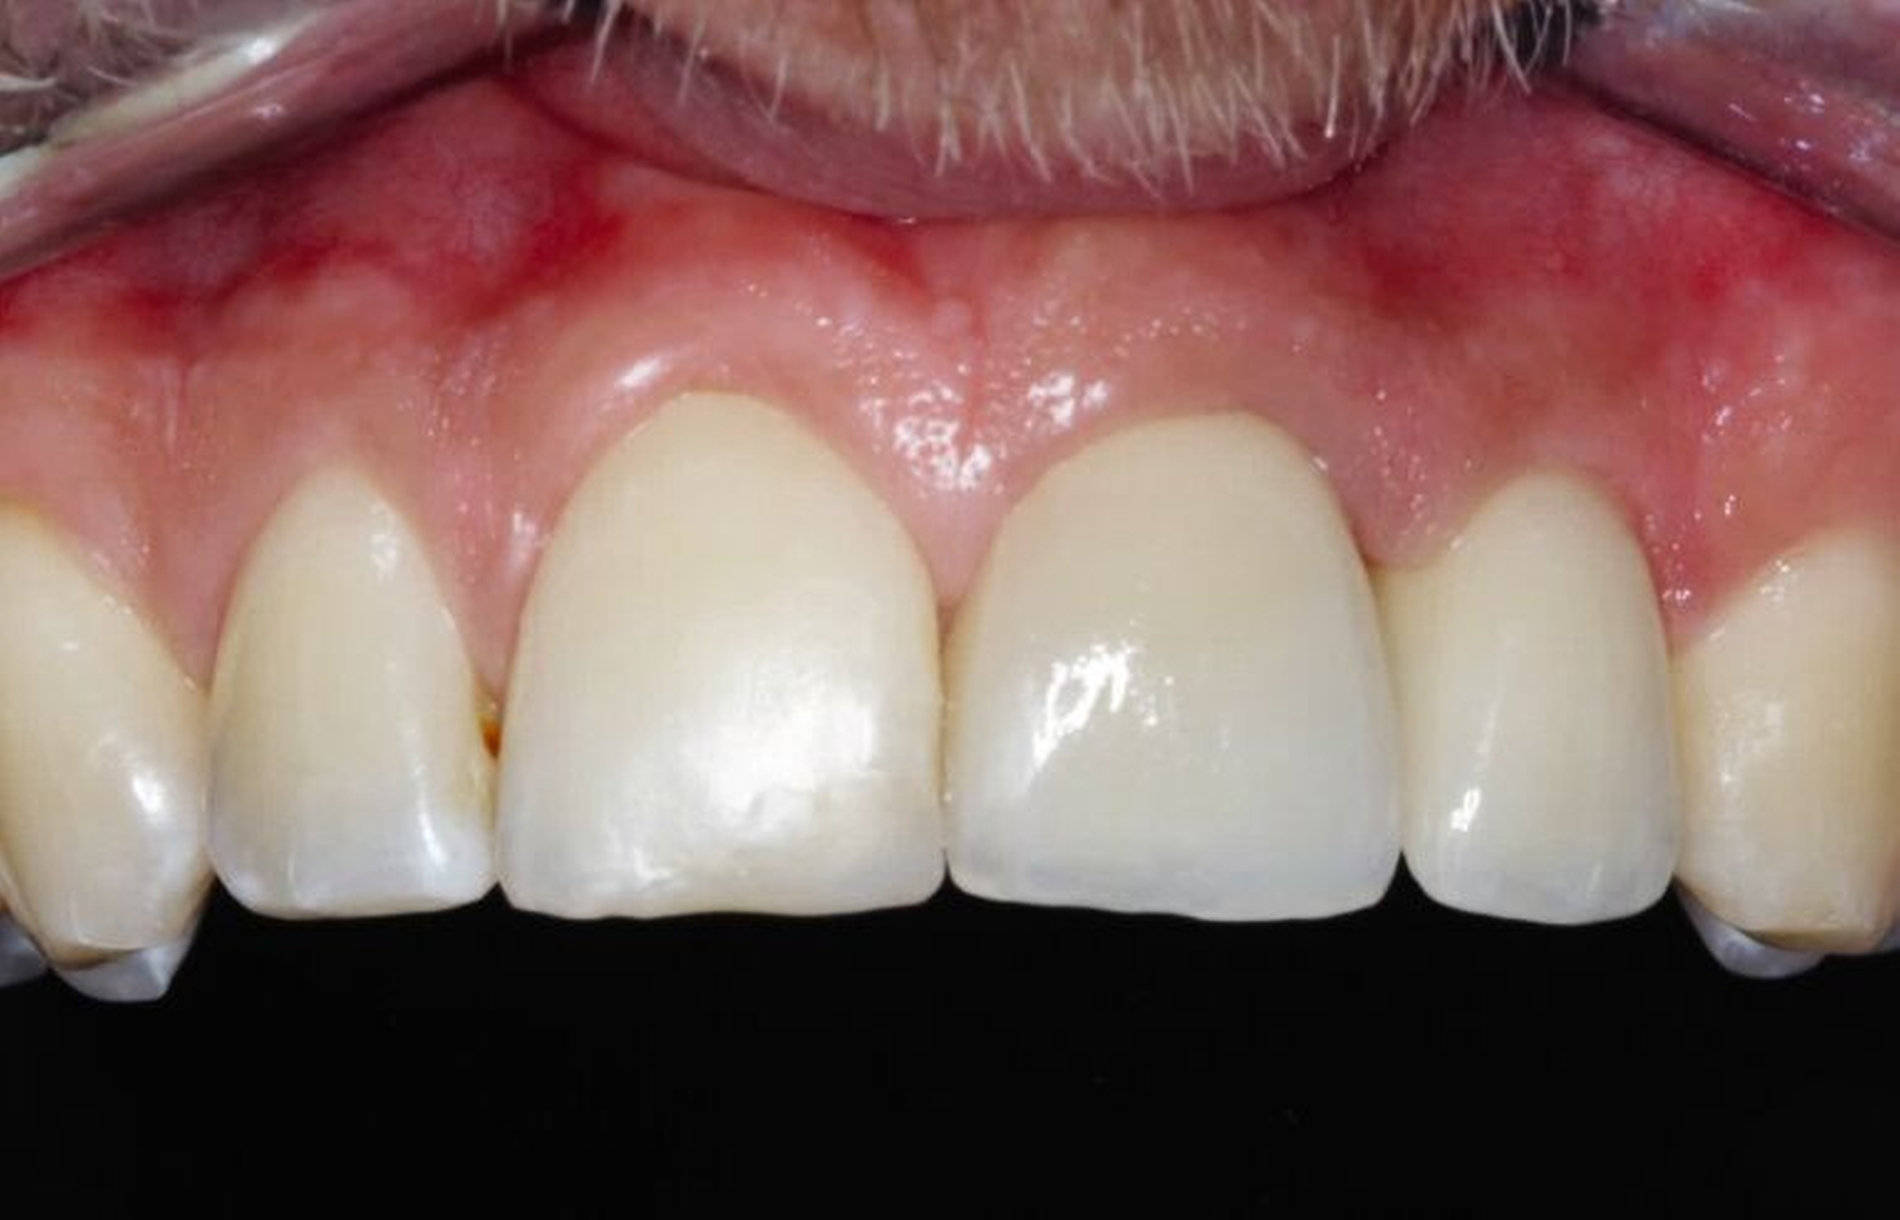

Die Zähne 11 und 21 wurden nach Abschluss der kieferorthopädischen Behandlung mit Lithiumdisilikat-Keramikkronen versorgt (Abbildungen 14 bis 16). Durch die Extrusion waren das Fassen der Frakturkante und die Etablierung des Ferrule-Effekts nun ohne Probleme möglich. Die Eingliederung der Arbeit konnte unter absoluter Trockenlegung erfolgen. Die nach dem Einsetzen angefertigte Einzelzahnaufnahme zeigt die präzise Adaptation der Kronen sowie Umbauprozesse des Alveolarkamms. Drei Jahre nach Therapieabschluss zeigt sich eine suffiziente klinische Situation (Abbildung 17).